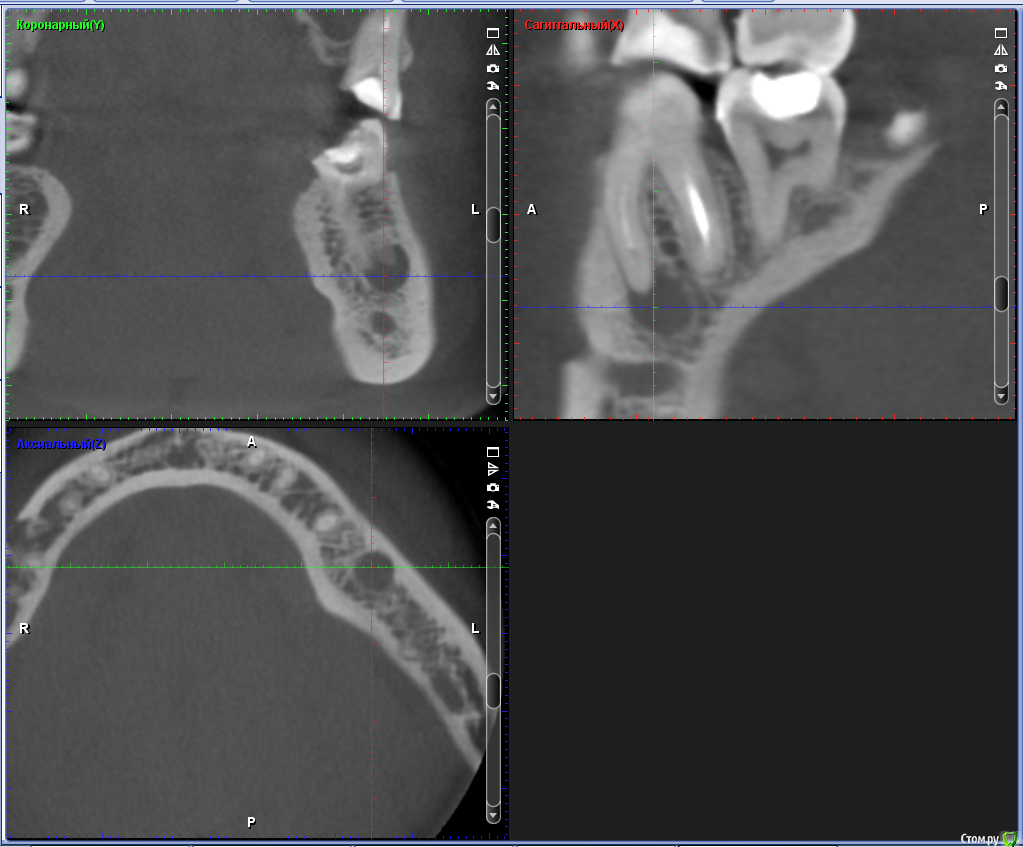

ClayMixer Опубликовано 18 ноября, 2016 Поделиться Опубликовано 18 ноября, 2016 (изменено) Здравствуйте! Вопросы по двум зубам (36 и 26): 1. Киста (36-ой зуб).Консультировалась у нескольких врачей. Мнения разные. От "можно поставить вкладку и коронку на n-ное количество времени до удаления; эту кисту не вылечить", до: "только удаление, желательно быстрее". 1) Можно ли вылечить этот зуб? И каков процент успеха?2) Есть ли смысл лечить зуб и ставить вкладку и коронку или лучше удалить и делать имплант? После того, как 36 зуб подготовили под вкладку - бывали неприятные непонятные ощущения (похожие на импульсы), не острые (длительностью 3 нед.) Вроде после этого времени стали утихать понемногу. 2. Инородное тело (обломок инструмента) в 26-м зубе.Врачи пытались извлечь его (без микроскопа) - безуспешно. Канал, в котором "застрял" инструмент не до конца "пройден".Критично ли это? Какова вероятность воспаления? (теперь патологический страх появления кисты ) Теоретически можно ставить вкладку и коронку? Ходила таким трансформером больше 5-ти лет, не беспокоил вообще. После попыток врачей достать инструмент также бывали неприятные непонятные ощущения (похожие на импульсы), не острые (длительностью 3 нед.) Вроде после этого времени стали утихать. При простукивании коронки обеих зубов болевых ощущений вроде не наблюдалось. Результаты КТ https://cloud.mail.ru/public/Fhy4/ESmeyU9hp Изменено 18 ноября, 2016 пользователем ClayMixer Ссылка на комментарий

ClayMixer Опубликовано 18 ноября, 2016 Автор Поделиться Опубликовано 18 ноября, 2016 26-ой зуб Ссылка на комментарий